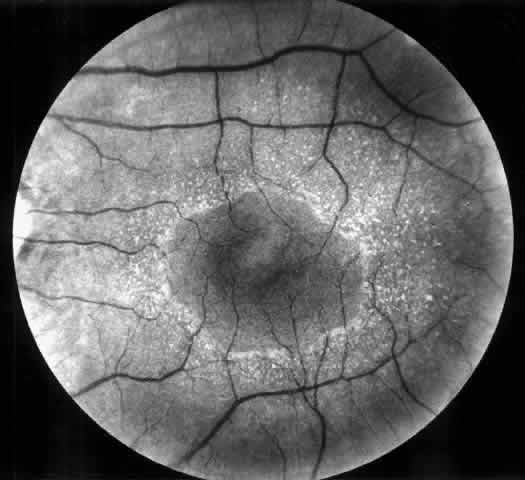

All cystinotic patients have ocular involvement, and older patients with nephropathic cystinosis are at risk of severe ocular complications. In nephropathic cystinosis, crystal deposits usually appear in the cornea within the first year of life. Initially, crystals can be identified in the anterior peripheral part of the cornea by slit lamp biomicroscopy. With time, progressive accumulation of crystals occurs throughout the corneal stroma, inducing photophobia even in young children and provoking a hazy, ground-glass appearance of the cornea in older patients.36 Crystal deposits are also formed in conjunctiva, iris, and retinal pigment epithelium.37 Focal degeneration of the retinal pigment epithelium with patchy depigmentation of the fundus may appear early in life and is generally present by age 7.37 The fundus lesions are bilateral and symmetric and involve mainly the periphery, although some patients also develop atrophic macular changes (Fig. 3). Abnormal retinal function with reduced or extinguished responses on electroretinograms and decreased visual acuity are frequent complications in older cystinotic patients.37,38 Several other complications have been described in patients with nephropathic cystinosis, including superficial punctate keratopathy, recurrent erosions, corneal vascularization, band keratopathy, tight miosis, posterior synechiae, and pupillary-block glaucoma.35,37–39

Fig. 3. Cystinotic fundus changes in a 19-year-old patient, demonstrating a pale optic disc and numerous peripheral and macular small white spots at the level of the retinal pigment epithelium. Fluorescein angiography confirmed marked degenerative changes of the retinal pigment epithelium with macular, peripapillary, and peripheral window defects.